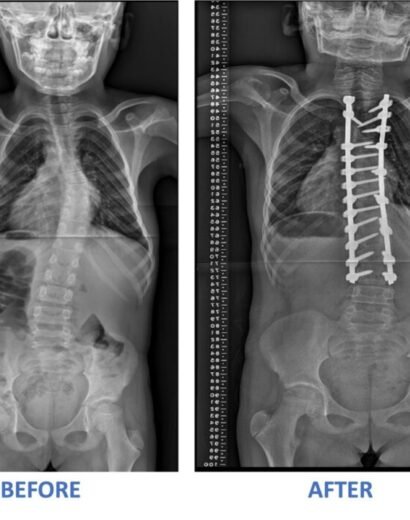

Success Stories

As Ghana’s leading orthopaedic and spine care hospital, we specialize in world-class treatments, cutting-edge surgeries, and personalized rehabilitation to help you move pain-free. Experience top-tier medical expertise, advanced diagnostic services, and patient-centered care in a state-of-the-art facility. Your health, our commitment.

FOCOS mission is to provide comprehensive, affordable orthopaedic care to those who would not otherwise have access to such treatment. Specifically, we strive to improve accessibility to top-notch surgical and non-surgical care for patients who suffer from debilitating musculoskeletal conditions, such as complex spine deformities and pediatric orthopedic problems, in underserved areas. It all began as a dream of the founder to see the best care reach the underserved in his native country, Ghana and the sub-Saharan region.